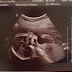

I can't believe I'm 20 weeks already, this pregnancy is whizzing by. The first trimester was taken up with the wedding then I found weeks 12-16 dragged; I was in a weird limbo but then time suddenly sped up and next thing we know we were sat at the Hospital ready for our 20 week scan.

This scan was a bit different from the 12 week one as a student did it so it took longer then had to be checked to make sure she didn't miss anything. It did mean we got a double scan but it took ages - almost an hour in fact. The baby was being awkward too covering his face and had his legs crossed so getting the gender was hard but once the legs opened there was no mistaking it haha! We both felt a bit anxious at one point as the student didn't say much but once everything was double checked we were told all was fine and could breathe a sigh of relief.